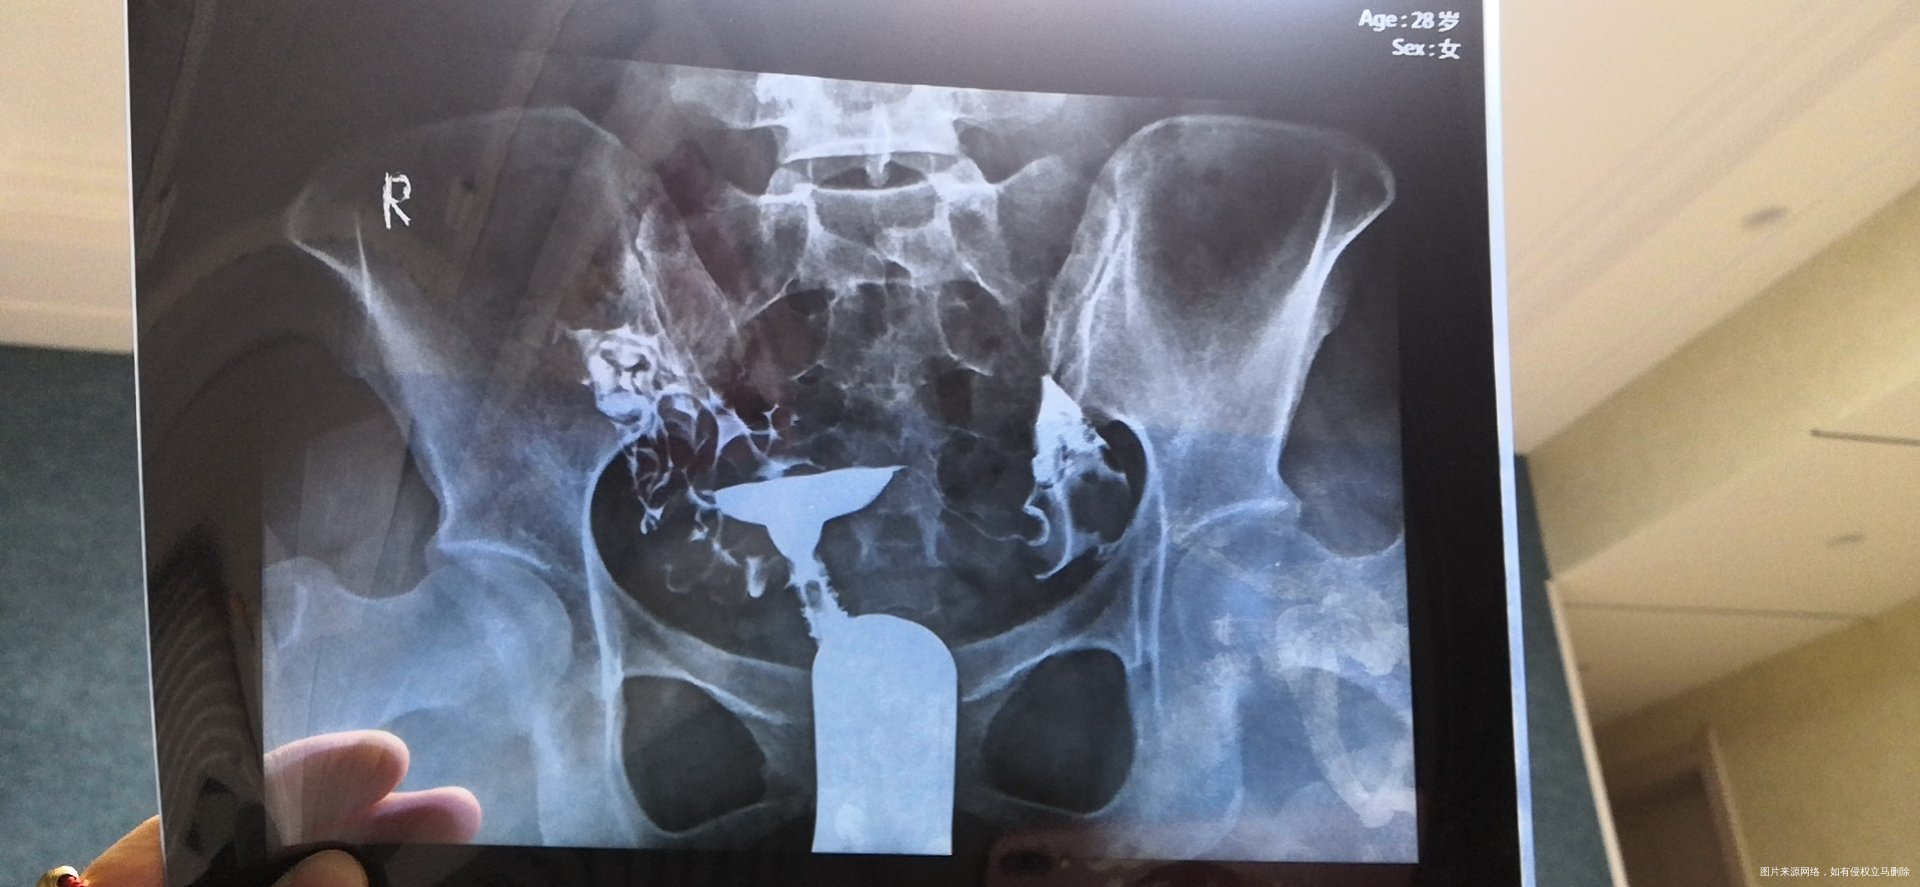

可以帮忙看一下输卵管片子吗?4个图的是第一次造影,去年九月做的,剩下两张图是今年五月份做的,现在一直在吃中药调理!

您好,今年拍的片子比去年好一点,但是从片子上看今年的双侧伞瑞仍然粘连

是的,可以做腹腔镜手术。